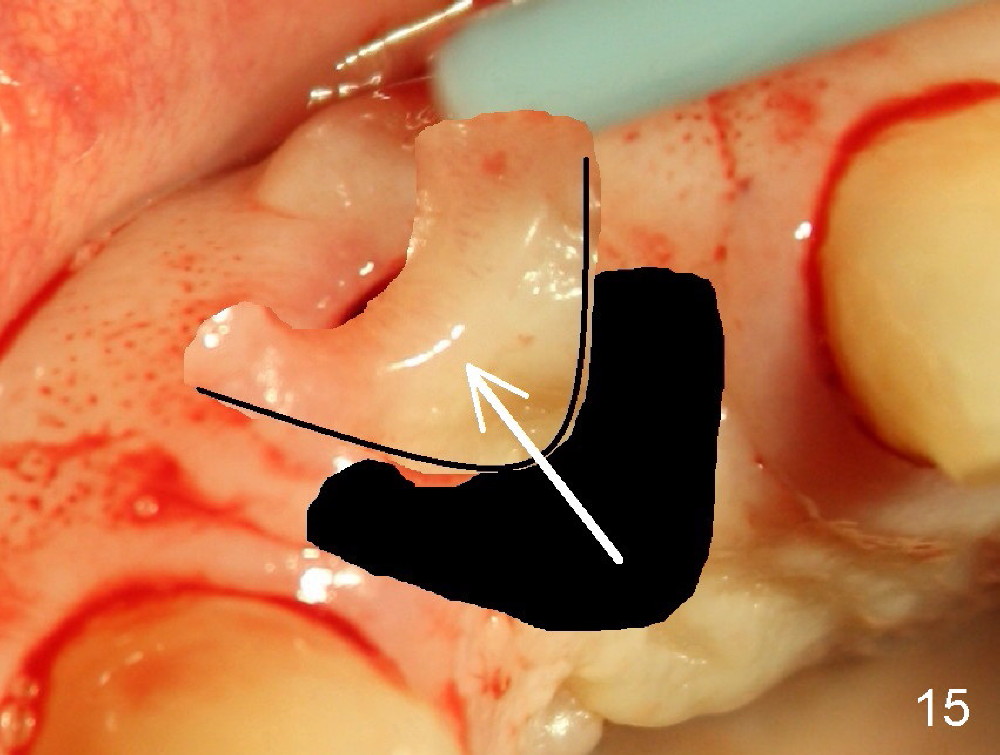

If a larger incision were made (Fig.14) and the flap were dissected freely (Fig.15), the buccal tissue deficiency would be less (Fig.16). Follow up is shown 2 3.